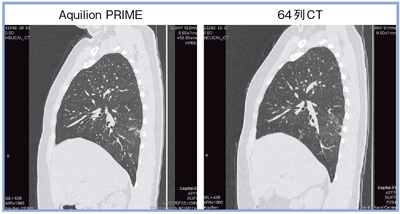

肺の画像を64列CTと比較すると,Aquilion PRIMEでは葉間などがきれいに描出され,腫瘍の辺縁も明瞭である(図3)。

図3 高密度サンプリングによる画質の比較(肺のサジタル画像)